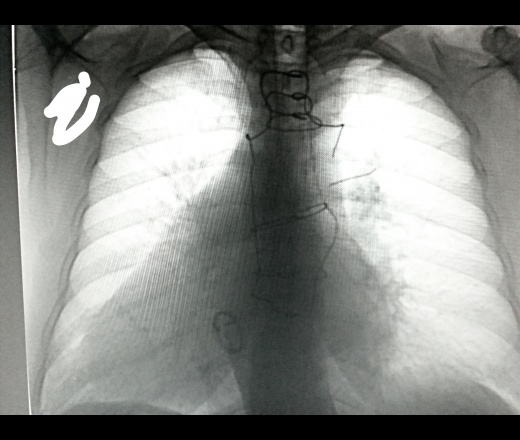

Мужчина 1950 г р. Проф ФЛГ. Операция по поводу имплантации искуственного клапана. Читал снимки и вот такое обнаружил! Слетела проволока с грудины:(. Коллеги посмотрите пожалуйста может кто видел подобное? Что делать?

Кардиохирургия, имплантированный митральный клапан.Дефект металлоконструкции.

Можно написать "разрыв серкляжного шва". Назначить рентгенографию грудины в 2 проекциях, что бы посмотреть куда мигрировала эта фигнюха. Иногда они впиваются в мягкие ткани и вызывают отек и боли...